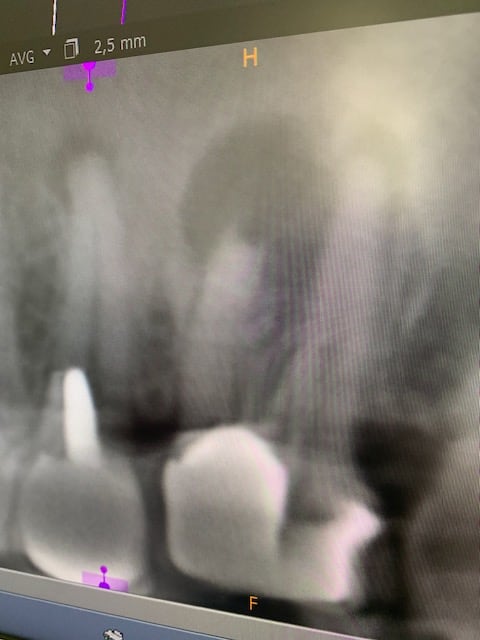

c est vrai que les radios post op des endos seraient informatives.

Oui, bien sûr qu’il y a des radios ! Tu ne fais pas un bridge 13/17 sans radios, pour qui prends tu notre consoeur ?

Pas de conclusions hâtives, attendons les radios.